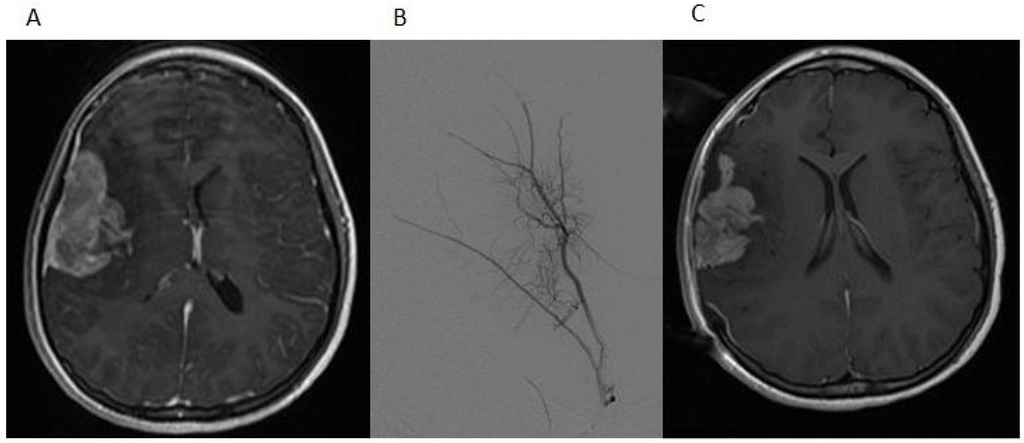

Two weeks after the completion of radiation therapy, the patient developed painless bilateral cervical adenopathy with several firm, immobile, right posterior cervical lymph nodes approximately 2 cm in the greatest diameter. One week later, the patient developed midline back pain primarily in the lumbar area and also pancytopenia. An MRI demonstrated the bilateral cervical adenopathy, as well as lytic vertebral lesions of the cervical, thoracic and lumbar spine with multifocal bone marrow involvement (Figure 4A). A mass deep to the right sternocleidomastoid muscle was excised. Microscopically, there was an infiltrated lymph node along one edge, and the mass consisted of sheets of poorly-differentiated metastatic tumor cells positive for GFAP and rarely for synaptophysin. A right iliac crest bone marrow biopsy was performed, and it showed 60% infiltration with GFAP-positive and nestin-positive tumor cells, while synaptophysin was focally positive (Figure 5).

Figure 4. (A) The sagittal STIR (short TI inversion recovery) MRI image demonstrates extensive new osseous metastases with multiple pathologic compression fractures of the lumbar spine; (B) The sagittal T-weighted MRI image demonstrates interval mild improvement in bone marrow signal abnormality after treatment; the fatty replacement of tumor is shown by white arrows.

This pattern of mutations has been reported in high-grade pediatric gliomas and supported this diagnosis. The presence of a BRAF V600E mutation suggested additional therapeutic options. Following the discussion of this case at the Rutgers Cancer Institute of New Jersey Molecular Tumor Board, vemurafenib (960 mg BID), an oral BRAF inhibitor, was added to her treatment regimen. She developed a macular rash on the extremities five days after starting vemurafenib, while both back pain and pancytopenia improved and the cervical adenopathy regressed. An MRI of the spine also showed partial regression of the bone marrow disease (Figure 4B). After four weeks of this treatment, she developed worsening back and hip pain, and the size of the cervical adenopathy increased. Her chemotherapy regimen was changed to carboplatin, which did not result in a sustained response. Comfort care was pursued, and the patient subsequently died of her disease, 11 months after symptoms began and 10 months after the initial craniotomy. No autopsy was performed.